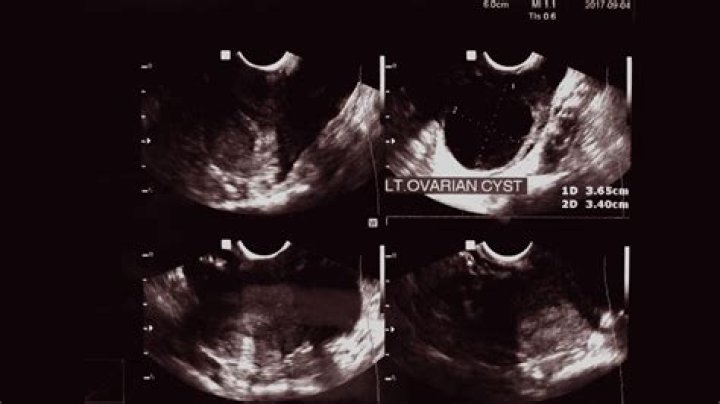

How do you check if you have cysts on your ovaries?

Your doctor can detect an ovarian cyst during a routine pelvic examination. They may notice swelling on one of your ovaries and order an ultrasound test to confirm the presence of a cyst.

How does a gyno check for ovarian cysts?

If your gynecologist suspects that your symptoms could be due to ovarian cysts the best way to diagnose these cysts is through a pelvic exam or by performing an ultrasound. The ultrasound will allow your doctor to examine the abdomen in detail to see if cysts are present.

Can an ultrasound detect ovarian cancer?

Ultrasound is often the first test done if a problem with the ovaries is suspected. It can be used to find an ovarian tumor and to check if it is a solid mass (tumor) or a fluid-filled cyst. It can also be used to get a better look at the ovary to see how big it is and how it looks inside.